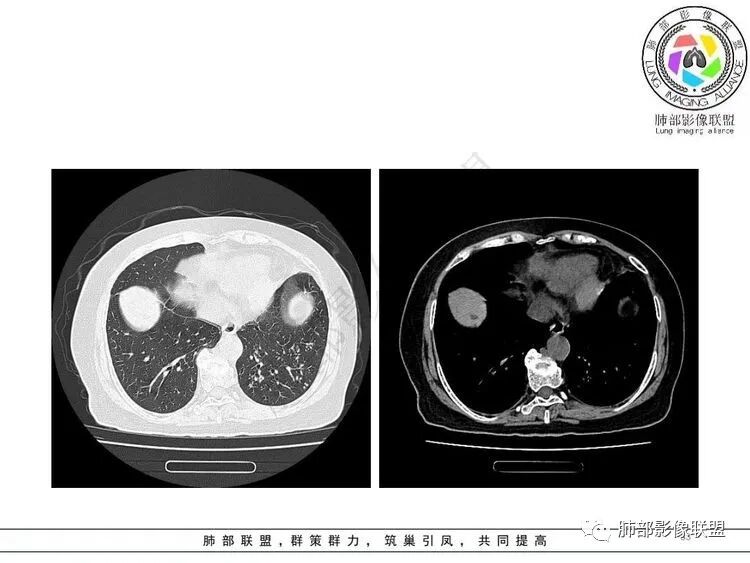

经痰涂片及CTPA检查的结果:肺结核合并肺栓塞。

痰涂片:抗酸杆菌++++。痰结核菌DNA测定:阳性。

影像特点支持结核。气促、左上肺病灶似乎不能解释I型呼吸衰竭加上D—二聚体明显升高、肺动脉干增粗,临床需要想到二元可能:肺结核合并肺栓塞可能,需要完善CTPA明确有没有肺栓塞,因为急性肺栓塞是急危重症。

D-二聚体升高,肺动脉成像等明确患者肺栓塞的存在!